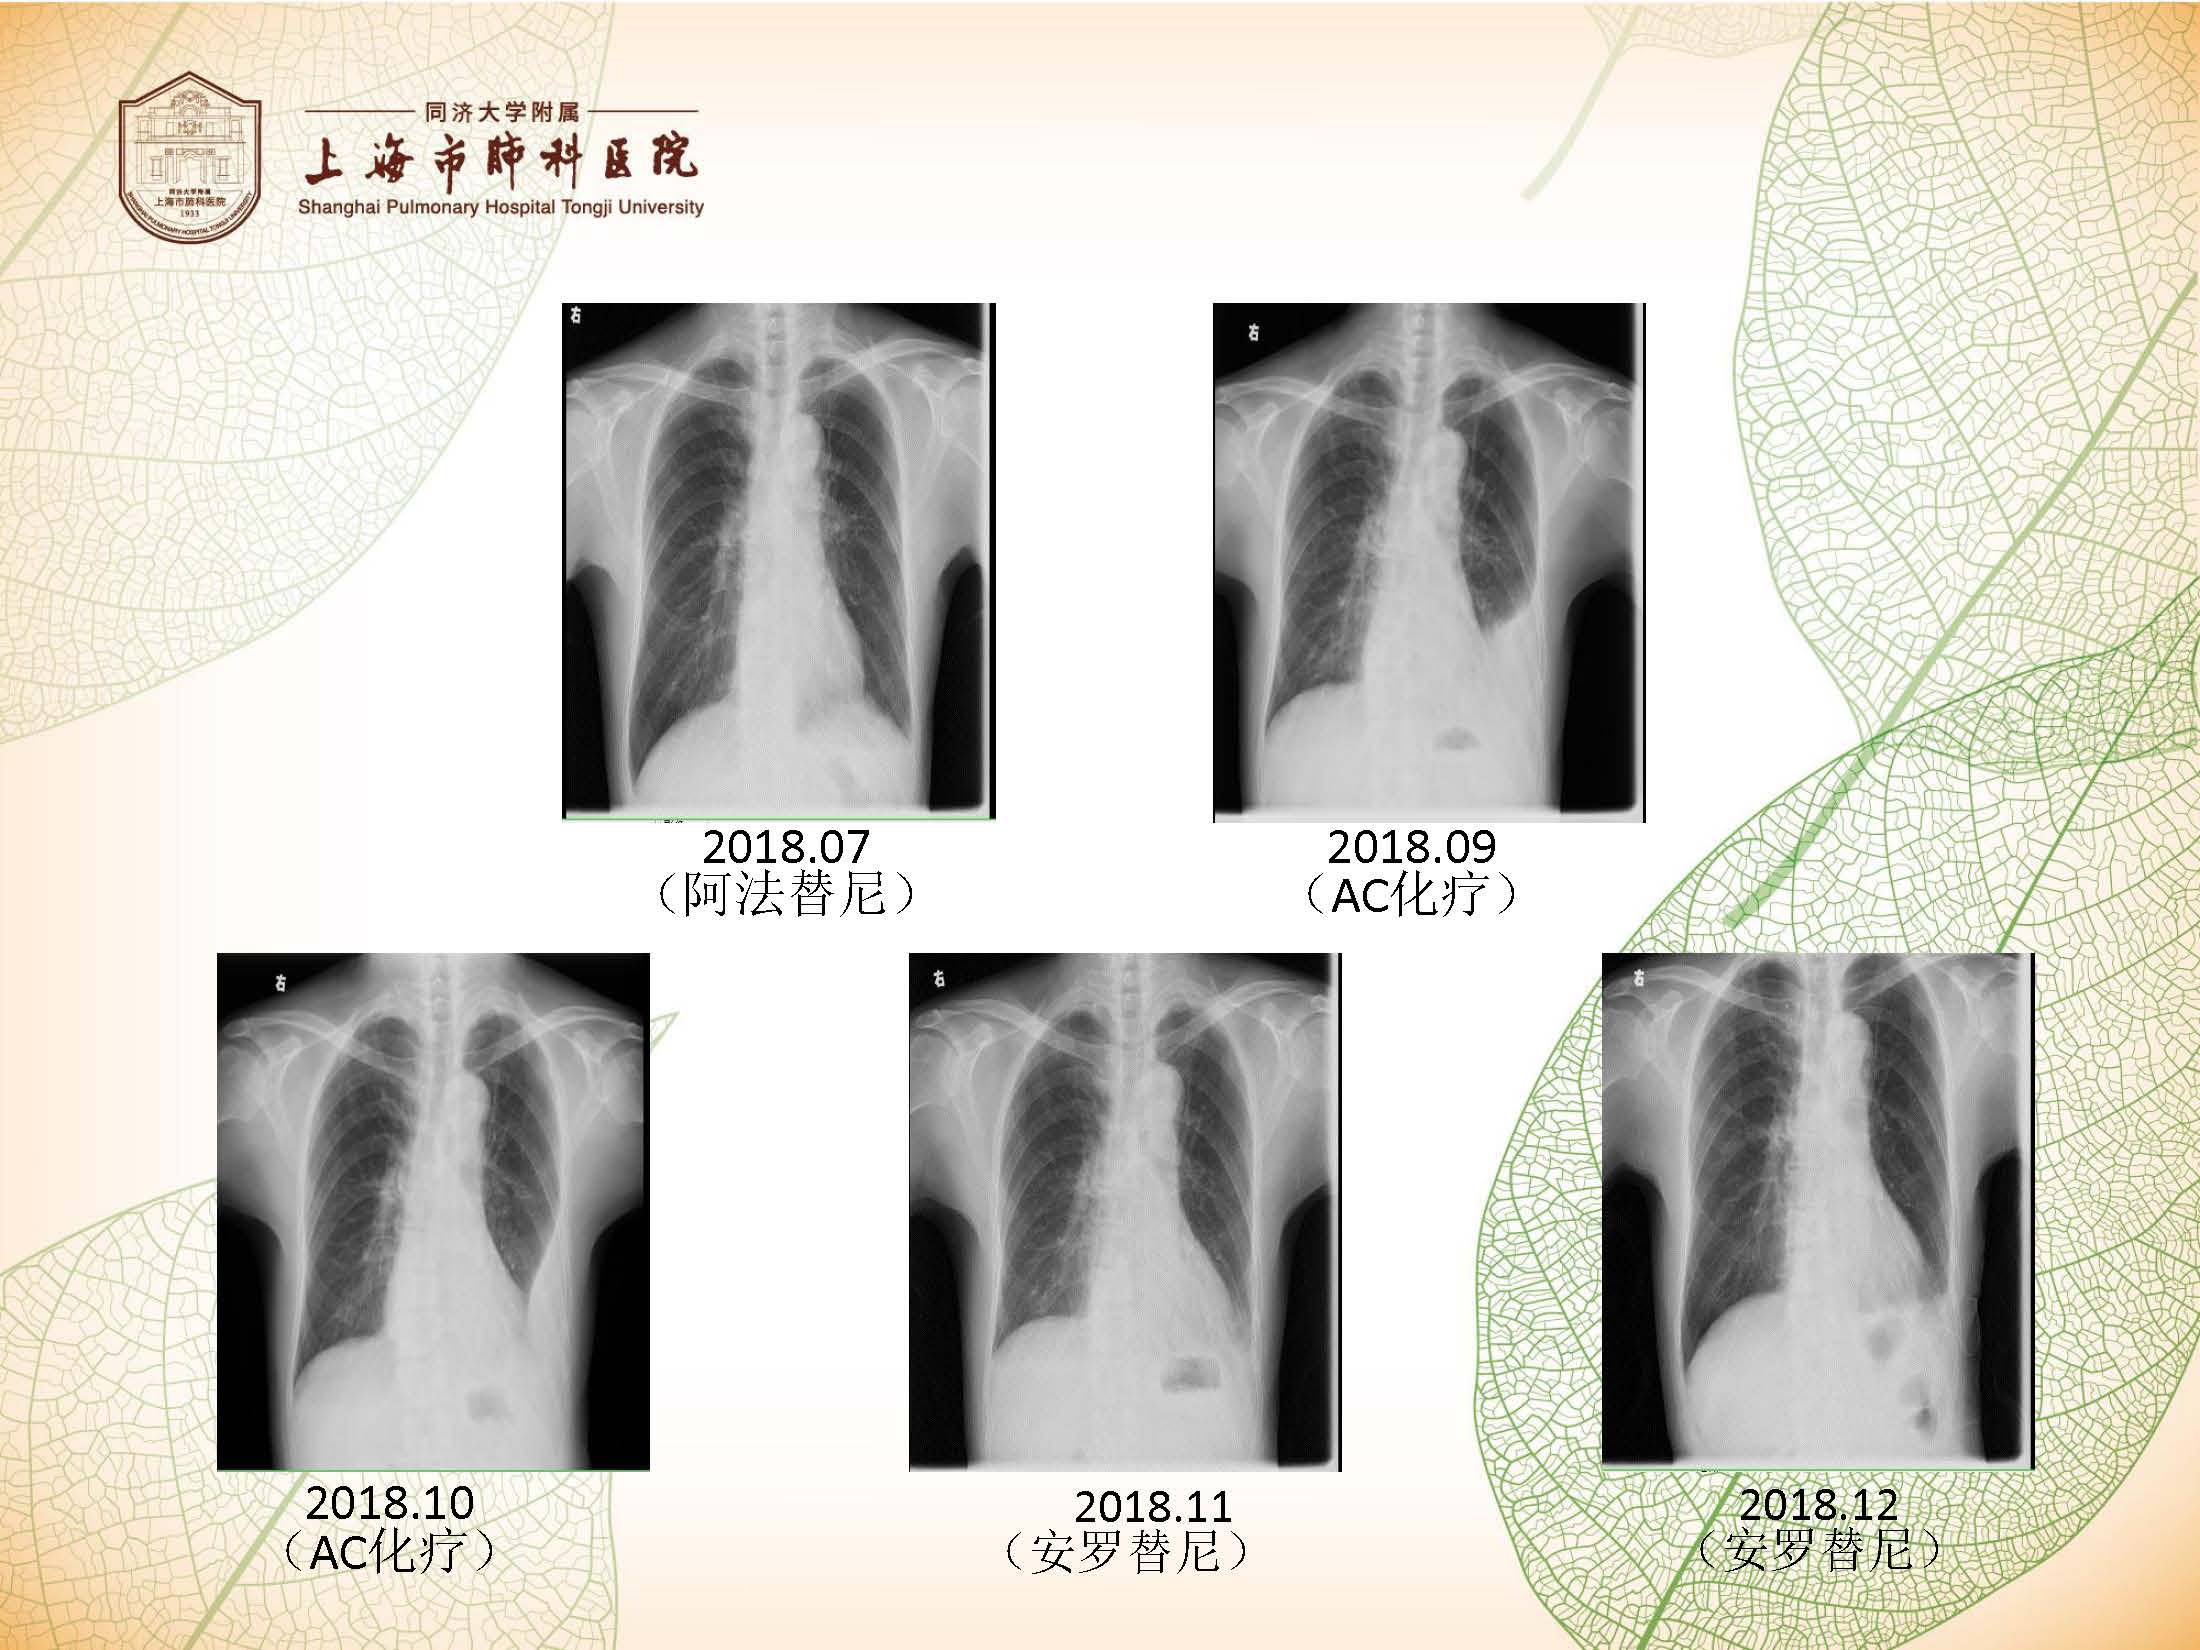

安罗替尼病例分享(罗洁)

病例来源:上海市肺科医院肿瘤科 罗 洁